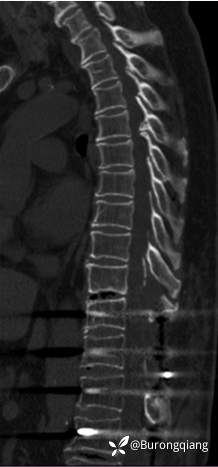

简要病史:患者述2年前无明显诱因出现双下肢大腿憋胀不适症状。外院进一步检查后诊断胸腰椎椎管狭窄,于外院行胸腰椎多节段椎管减压内固定手术治疗,术后症状改善明显,术后10个月再次逐渐出现双下肢麻木无力症状,左侧症状明显,行走时偶有打软腿不适,1年前摔倒致左踝关节骨折,给予内固定手术治疗,术后一直未能下地活动,双下肢麻木无力明显,二便正常。采取保守对症治疗,症状近来逐渐加重。

临床诊断:胸椎管狭窄

术后复查